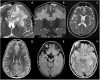

Relapsing demyelinating syndromes (RDS) in children encompass a diverse spectrum of entities including multiple sclerosis (MS) acute disseminated encephalomyelitis (ADEM), aquaporin-4 antibody associated neuromyelitis optica spectrum disorder (AQP4-NMOSD) and myelin oligodendrocyte glycoprotein antibody disease (MOG-AD). In addition to these, there are "antibody-negative" demyelinating syndromes which are yet to be fully characterized and defined. The paucity of specific biomarkers and overlap in clinical presentations makes the distinction between these disease entities difficult at initial presentation and, as such, there is a heavy reliance on magnetic resonance imaging (MRI) findings to satisfy the criteria for treatment initiation and optimization. Misdiagnosis is not uncommon and is usually related to the inaccurate application of criteria or failure to identify potential clinical and radiological mimics. It is also notable that there are instances where AQP4 and MOG antibody testing may be falsely negative during initial clinical episodes, further complicating the issue. This article illustrates the typical clinico-radiological phenotypes associated with the known pediatric RDS at presentation and describes the neuroimaging mimics of these using a pattern-based approach in the brain, optic nerves, and spinal cord. Practical guidance on key distinguishing features in the form of clinical and radiological red flags are incorporated. A subsection on clinical mimics with characteristic imaging patterns that assist in establishing alternative diagnoses is also included.